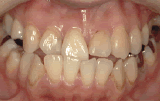

症例1/前歯が出ているのが気になる

【歯科治療前】